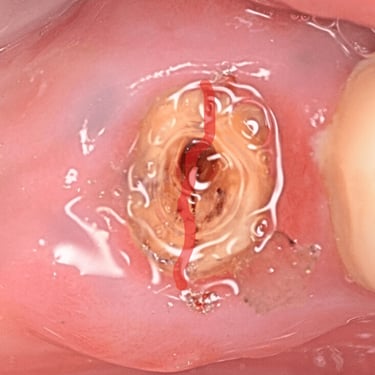

Perforación Radicular

Una perforación radicular es una abertura anormal en la raíz del diente, generalmente debido a un procedimiento dental fallido o una caries profunda.

Los pacientes pueden sentir dolor y notar hinchazón en la encía.

El tratamiento incluye la reparación de la perforación y el tratamiento de conducto. Es crucial reparar la perforación para evitar una infección.